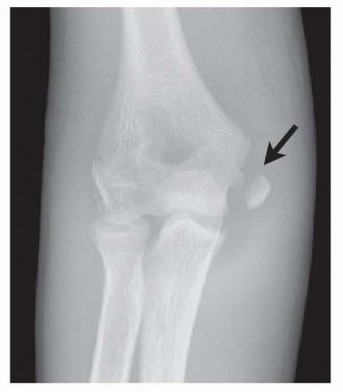

Medial epicondyle fractures represent approximately 11% to 20% of all pediatric elbow fractures, with a peak incidence occurring between the ages of 9 and 14 years. This demographic distribution corresponds directly to the vulnerability of the medial epicondylar apophysis prior to its final radiographic fusion, which typically occurs between 15 and 18 years of age. The pathophysiology of this injury is almost exclusively driven by an indirect, avulsion-type mechanism. During a fall on an outstretched hand (FOOSH) with the elbow in terminal extension, a massive valgus moment is generated. This force translates into extreme tensile stress across the medial structures. The robust flexor-pronator muscle mass and the anterior bundle of the ulnar collateral ligament (UCL) subsequently avulse the weaker apophyseal growth plate.

Direct trauma to the medial aspect of the elbow is a distinctly rare cause of this fracture pattern. Far more commonly, these fractures are intimately associated with an acute elbow dislocation, occurring in up to 50% of displaced medial epicondyle fractures. It is imperative to understand that the elbow may spontaneously reduce prior to the patient's arrival at the emergency department. Consequently, a high index of suspicion for a transient dislocation event must be maintained, as this implies a more extensive soft-tissue injury, including disruption of the lateral collateral ligamentous complex and the anterior capsule.

Clinical presentation is characterized by profound medial-sided ecchymosis, swelling, and point tenderness directly over the medial epicondyle. A meticulous physical examination is paramount, with a specific focus on neurovascular integrity and ligamentous stability. The ulnar nerve is intimately associated with the medial epicondyle, and preoperative documentation of its sensory and motor function is a strict medicolegal and clinical requirement. Furthermore, a careful valgus stress test—ideally performed under fluoroscopy or anesthesia—will unmask occult medial instability. Failure to recognize and address this instability in a high-demand patient will inevitably lead to chronic valgus extension overload, secondary radiocapitellar joint degeneration, and a profound inability to return to pre-injury levels of athletic performance.

Osseous Landmarks and Ossification Centers

For pediatric and adolescent patients, a thorough understanding of the radiographic appearance of the secondary ossification centers is crucial. The mnemonic CRITOE (Capitellum, Radial head, Internal/medial epicondyle, Trochlea, Olecranon, External/lateral epicondyle) dictates the chronological order of appearance. The medial epicondyle typically ossifies between ages 4 and 6 and fuses to the distal humeral shaft between ages 15 and 18. Because the apophysis is largely cartilaginous in younger patients, plain radiographs may grossly underestimate the true size of the avulsed fragment and the extent of the soft-tissue disruption. Furthermore, the surgeon must be acutely aware of the olecranon fossa, located immediately posterior and lateral to the medial epicondyle. Any hardware traversing the epicondyle must be directed anteriorly to avoid breaching the fossa, which would result in a catastrophic mechanical block to terminal elbow extension.